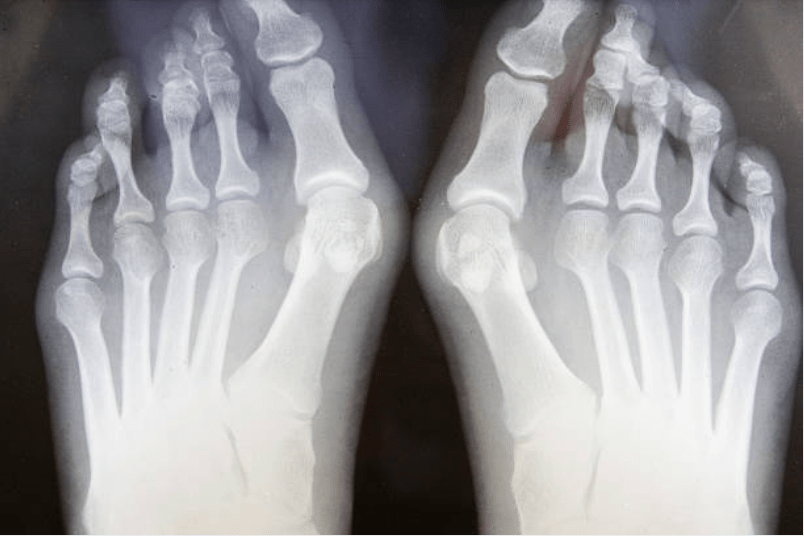

Chirurgie de l’hallux valgus

Cette chirurgie corrige la déformation du gros orteil.

En cas de douleurs, de gêne à la marche ou au chaussage.

Corriger la déformation, soulager la douleur et améliorer le confort.

Appui souvent possible avec chaussure adaptée. La récupération est progressive, avec un bon taux de satisfaction.

Radiographie

Rapide, accessible et peu contraignante, la radiographie est souvent prescrite en première intention pour orienter le diagnostic en analysant la structure osseuse et les articulations.

- Arthrose et usure articulaire

- Fractures et traumatismes osseux

- Déformations osseuses ou articulaires